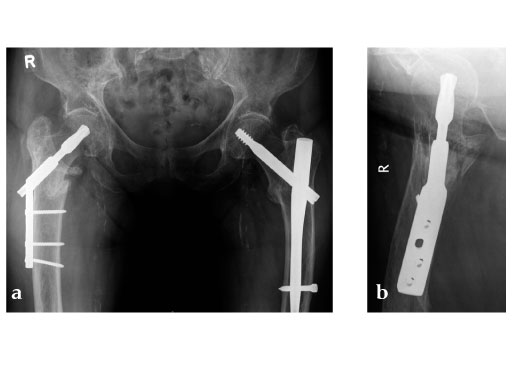

Case provided by Christoph Sommer, Chur, Switzerland

Müller AO Classification type 31-A2 fracture in an 83 year-old female with severe osteoporosis.